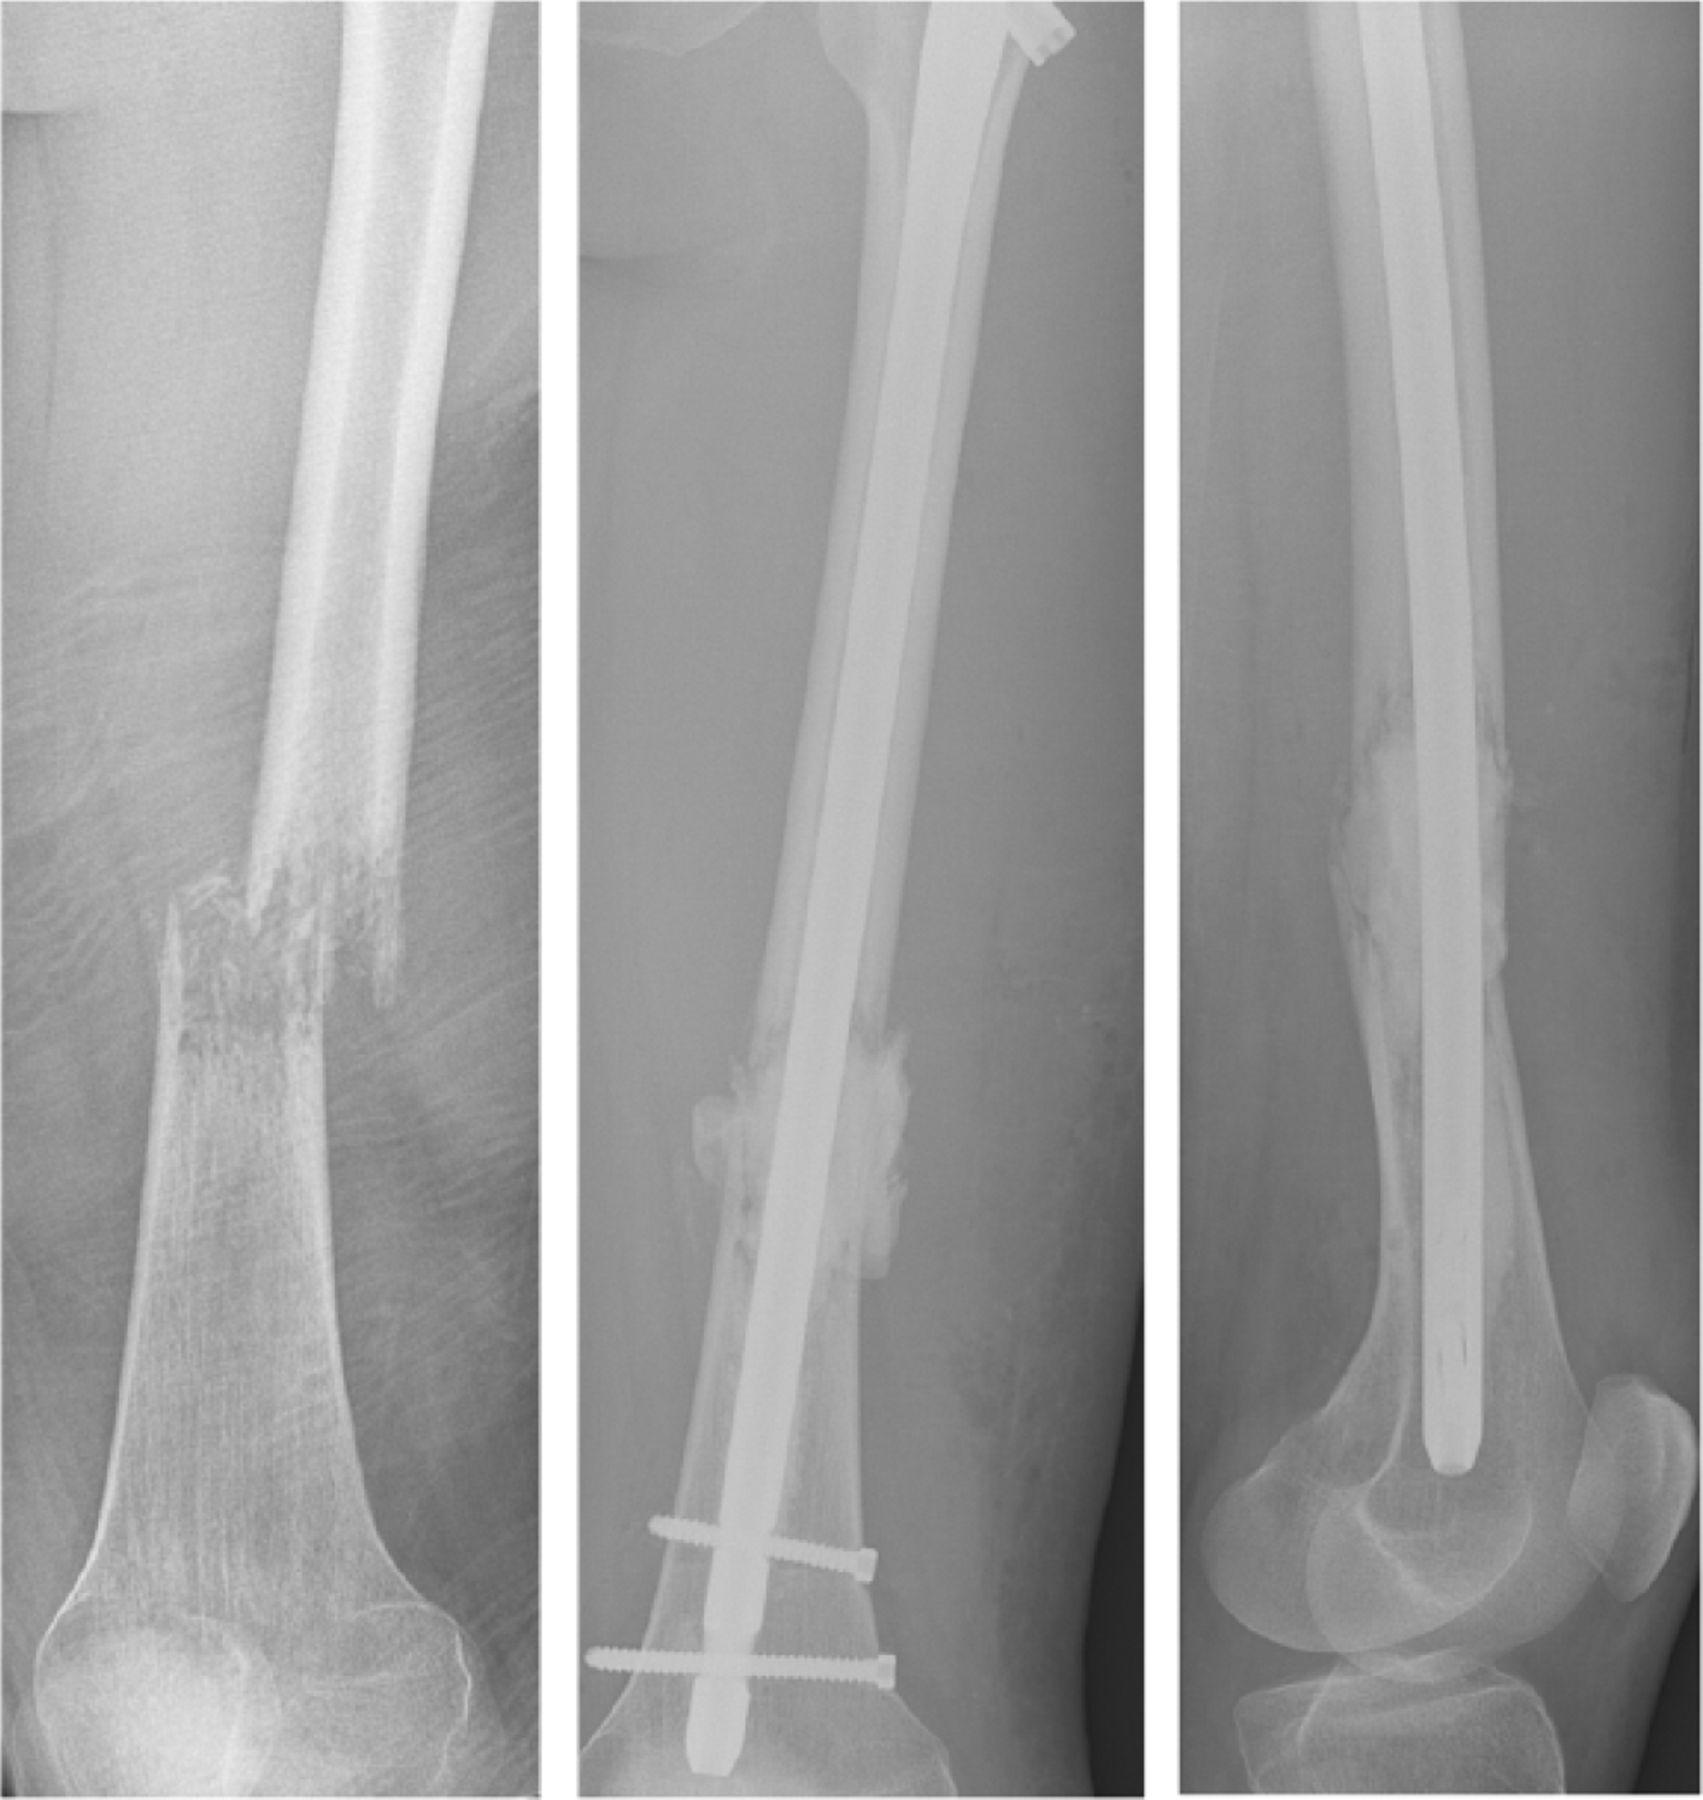

其中貧血是最常見的症狀,若出現頭暈、全身無力就要有所警覺。值得注意的是,多發性骨髓瘤可能侵犯到骨頭,造成骨骼破壞,所以不少人是在骨折就醫才發現罹病。

多發性骨髓瘤可能侵犯到骨頭,造成骨骼破壞,所以不少人是在骨折就醫才發現罹病。